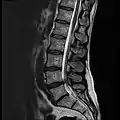

MRI lumbar spine with degeneration (sagittal T2 FRFSE)

MRI lumbar spine with degeneration (sagittal T1 FSE)